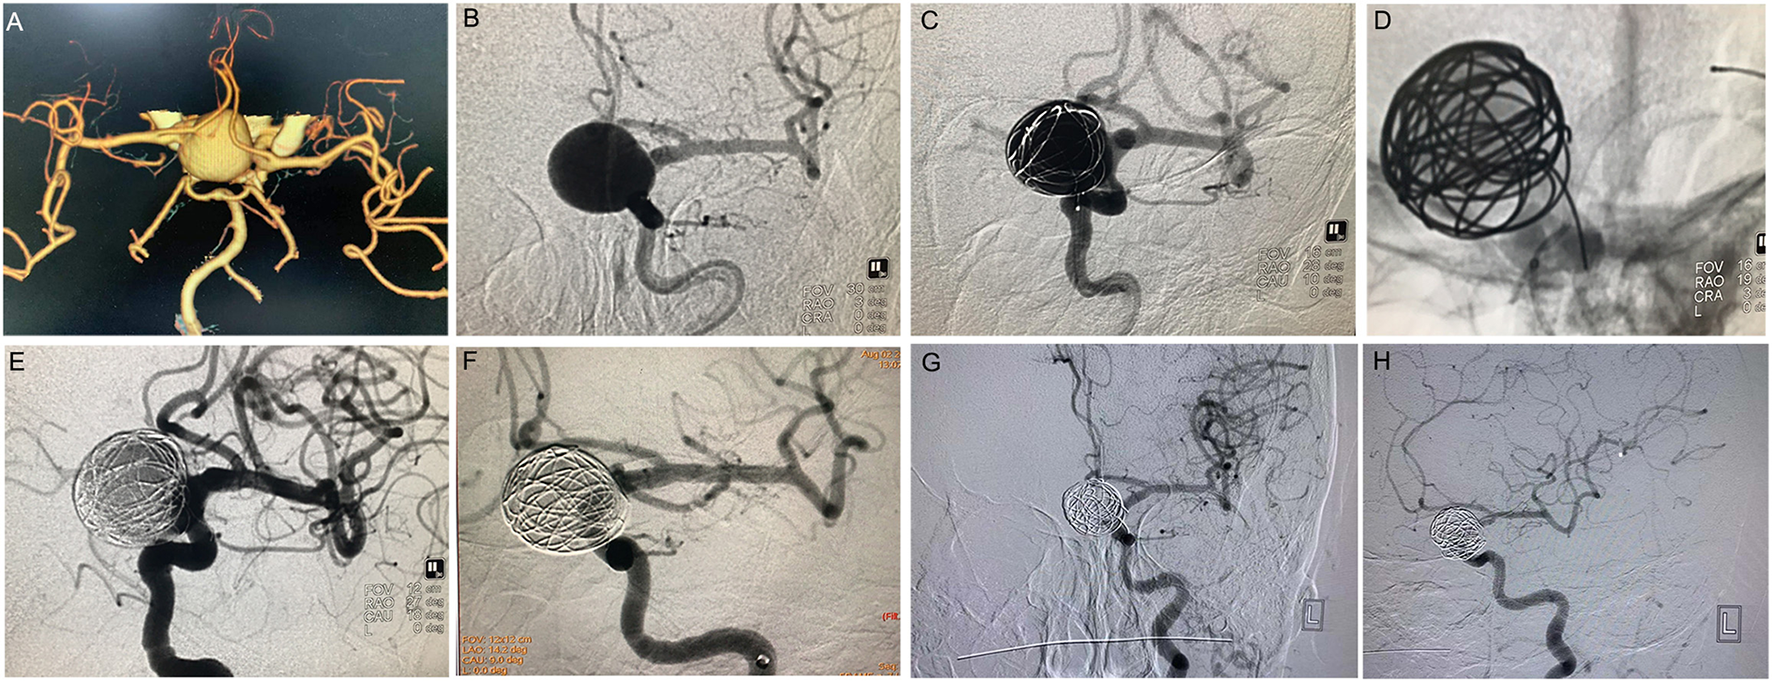

Figure 1

PipelineTM treatment of giant wide-necked aneurysm in the clinoid segment of the internal carotid artery. (A) CTA results show a giant wide-necked aneurysm in the clinoid segment of the left internal carotid artery; (B) working angle measurement indicates an aneurysm size of approximately 19.2 mm × 22.7 mm and an aneurysm neck of 15 mm; (C) first, a microcatheter is used to release the coil, and the coil is formed into a basket to support PipelineTM release; (D) release of the 4.0 × 25 PipelineTM; (E) the micro-guide wire is used to massage the stent to make the stent fit the wall completely; (F) 30 min later, the aneurysm is observed to be completely unremarkable on angiographic re-examination; and (G,H) 6 months after the procedure, DSA imaging re-examination shows complete healing of the aneurysm.